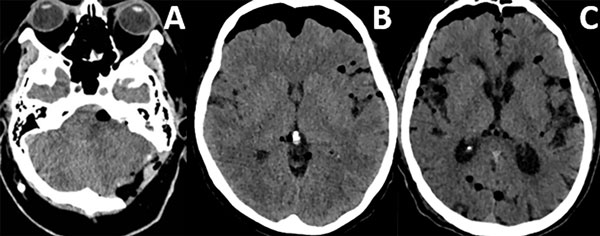

Patrones y grados de NE: NE subdural (Figura 1), se clasificó en 3 grados: leve (menor al espesor óseo), moderado (entre una vez y dos veces el espesor óseo) y severo (dos o más veces el espesor óseo). NE subaracnoideo (Figura 2), se clasificó en 3 grados: leve (confinado a cisternas basales), moderado (cisternas supratentoriales predominio unilateral), severo (generalizado). NE ventricular (Figura 3), se clasificó en: leve (en IV y/o III ventrículo), moderado (alcanzó VL), severo (alcanzó y dilató los VL).

Figura 2. Neumoencéfalo subaracnoideo. A) Leve. B) Moderado. C) Severo.